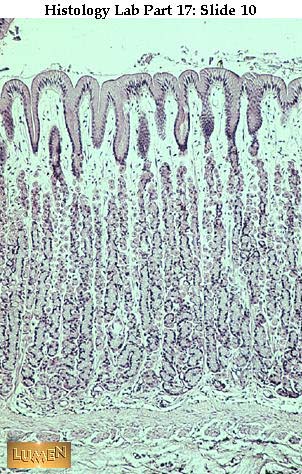

Q1 Where are these glands found?

Q2 What do the glands secrete?

Answer 1

fundus of the stomach

Answer 2

Mucus, HCl, gastrin,

intrinsic factor,

enteroglucagon,

serotonin,

somatostatin,

pepsinogen,

and lipase